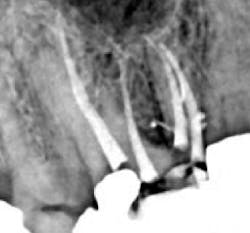

In 1989, I conceived of a way to radically simplify 3-D obturation.This new method collapsed Schilder's Vertical Condensation Technique of three-to-five heating and packing steps requiring five minutes per canal, into a downpack that required just two procedural steps and less than 15 seconds per canal to complete. While it was my intention was to simplify Schilder's procedure, the surprise result was a "centered" condensation technique that, despite the huge reduction in time and skills needed, actually provided superior obturation results that moved more gutta-percha into lateral complexities than vertical condensation (figures 2, 3, 4a, and 4b). (2)

Figure 2: My first Continuous Wave of Obturation result in a maxillary molar. Note the significant mid-root lateral canal filled off the MB2 canal, the mid-root isthmus filled between mesiobuccal canals, and the lateral canal filled off the MB1 canal.